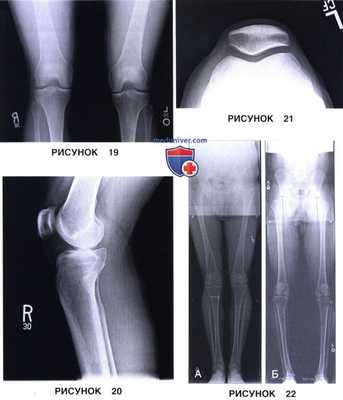

2. Рентгенография обоих коленных суставов стоя в положении сгибания 45° (по Rosenberg; рис. 19):

- Рентгенография в боковой проекции в положении сгибания 30° (рис. 20)

2. Рентгенография нижних конечностей на длинной кассете в положении стоя для оценки оси конечностей (рис. 22):

• Вальгусная и варусная деформация: рисунки 19 и 20

н) Вальгусная и варусная деформация: сужение суставной щели. При правильной укладке по рентгенограмме коленного сустава в ПЗ проекции можно оценить ширину суставной щели в медиальном и латеральном отделах сустава. Для этого следует измерить расстояние между наиболее дистальным участком мыщелка бедренной кости и задним краем мыщелка большеберцовой кости с каждой стороны. Сравнение получившихся расстояний друг с другом, с предыдущими измерениями или с измерениями противоположного коленного сустава позволяет выявить сужение суставной щели, а также вальгусную или варусную деформацию. При вальгусной деформации суставная щель латерального отдела коленного сустава уже, чем суставная щель медиального отдела; при варусной деформации —уже суставная щель медиального отдела (рис. 19 и 20).